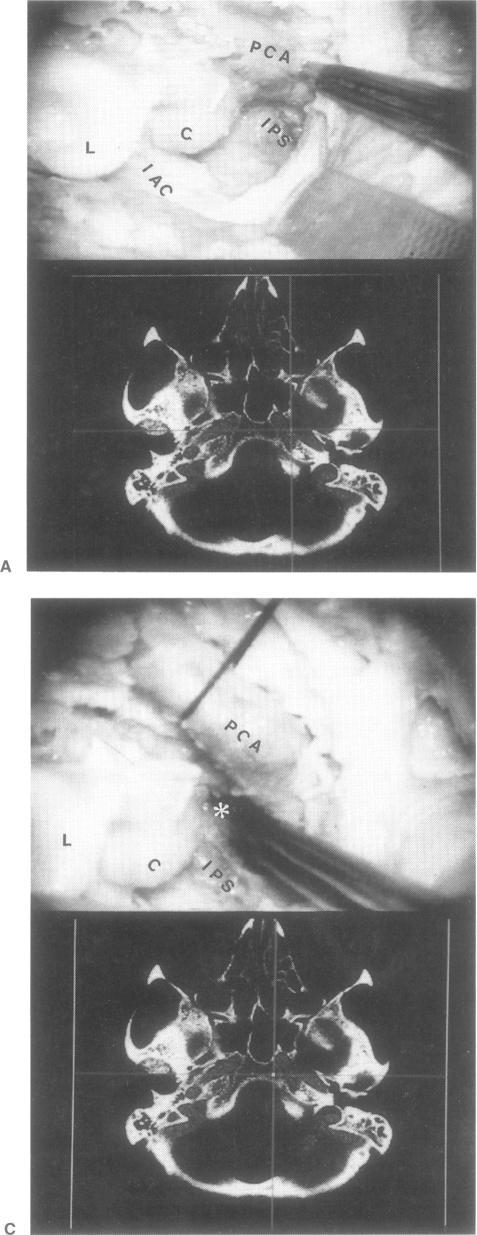

The applicability of an image guidance frameless system based on an opto-electronic sensor device in skull base surgery was explored in this study. Five embalmed heads with external fiducial markers placed in noncoplanar points were scanned (CT scan) and different skull base approaches were reproduced in these specimens. The opto-electronic system is comprised of an infrared camera, a local rigid body, and a 24-light-emitting diode probe attached to different surgical instruments. DOS-based calibration and transformation software and Unix-based surgical planning software were also used. The anatomic landmarks identified during the dissection were matched with the corresponding points derived from computed tomographic (CT) scans. This information allowed the surgeon to develop a three-dimensional representation of the surgical field and to anticipate the next anatomic structure encountered during the dissection. This infrared device operated in real time, is not affected by external factors with regard to its accuracy, and does not interfere with standard neurosurgical techniques. This frameless system is helpful in minimizing the risk of morbidity and provides an accurate guide during the approach, as well as unobstructed access to the surgical field.